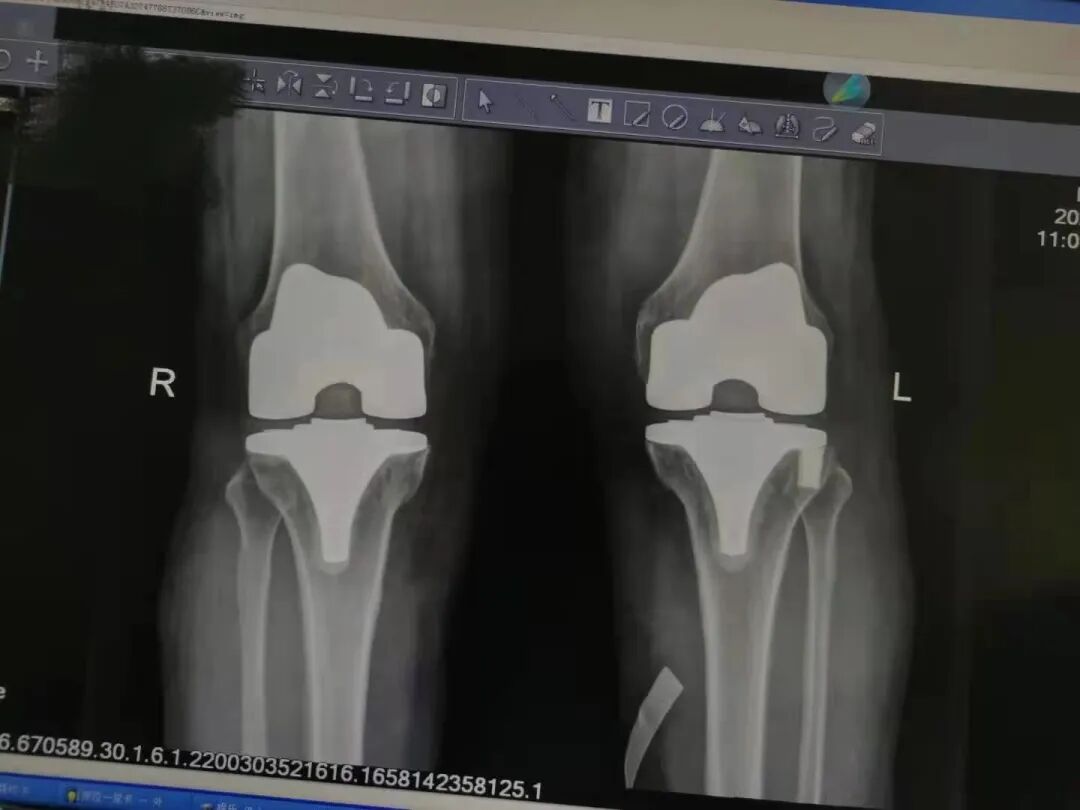

術(shù)后雙下肢X線片